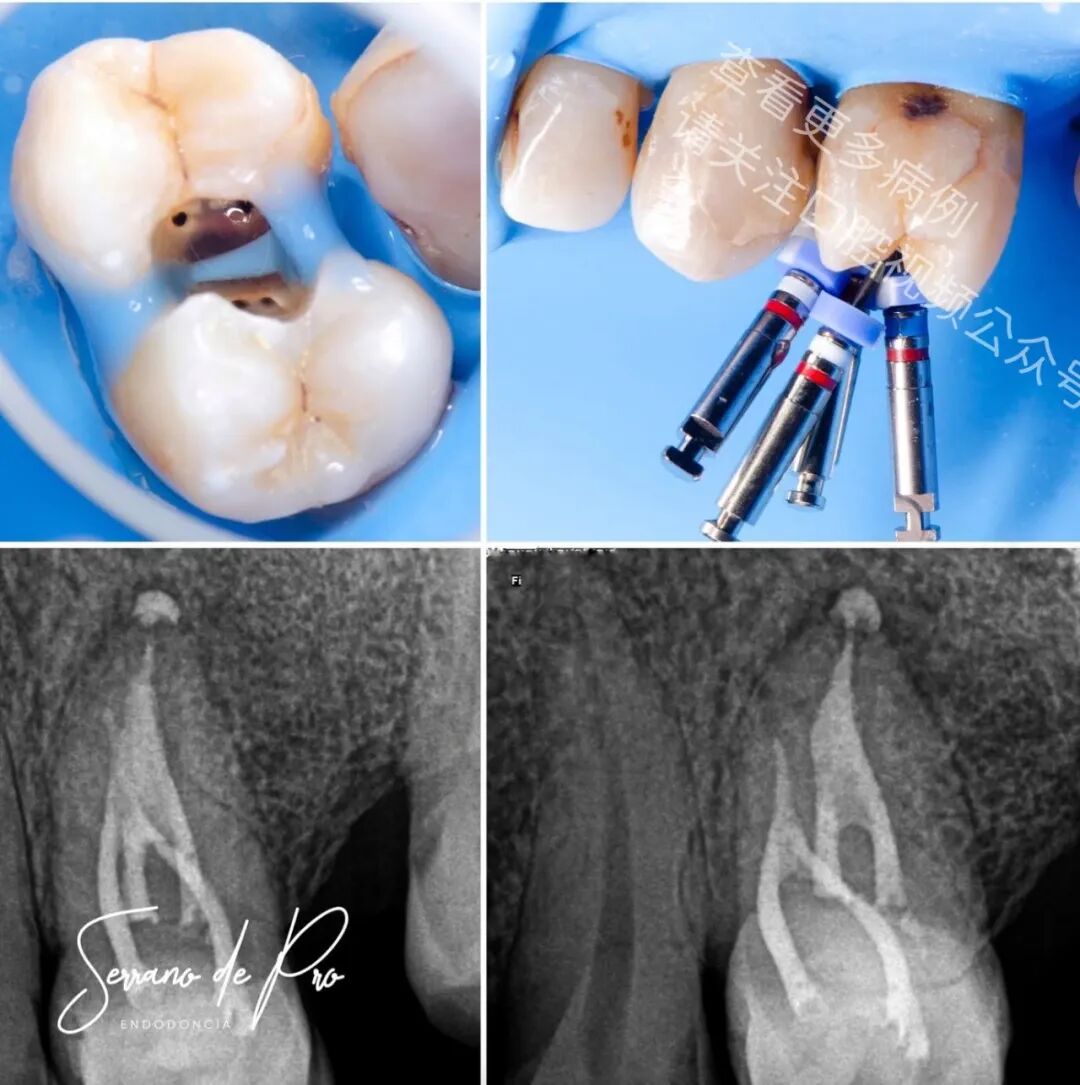

这是一个非常奇特的病例,24号牙和25号牙并非处于它们的正常位置,而是并排生长,拍出的X光片十分惊人。能如此清晰地看到根管充填的细节可不是每天都有的事。25号牙牙髓坏死,24号牙则患有严重的牙髓炎。

两颗牙都使用了来自FKG Iberia公司的Raceevo锉预备到30.04的锥度,并用Avalon Biomed公司的Neosealer Flo封闭剂以及Zarc4endo公司的产品配合WaveOne垂直加压(WVC)技术进行根管充填。